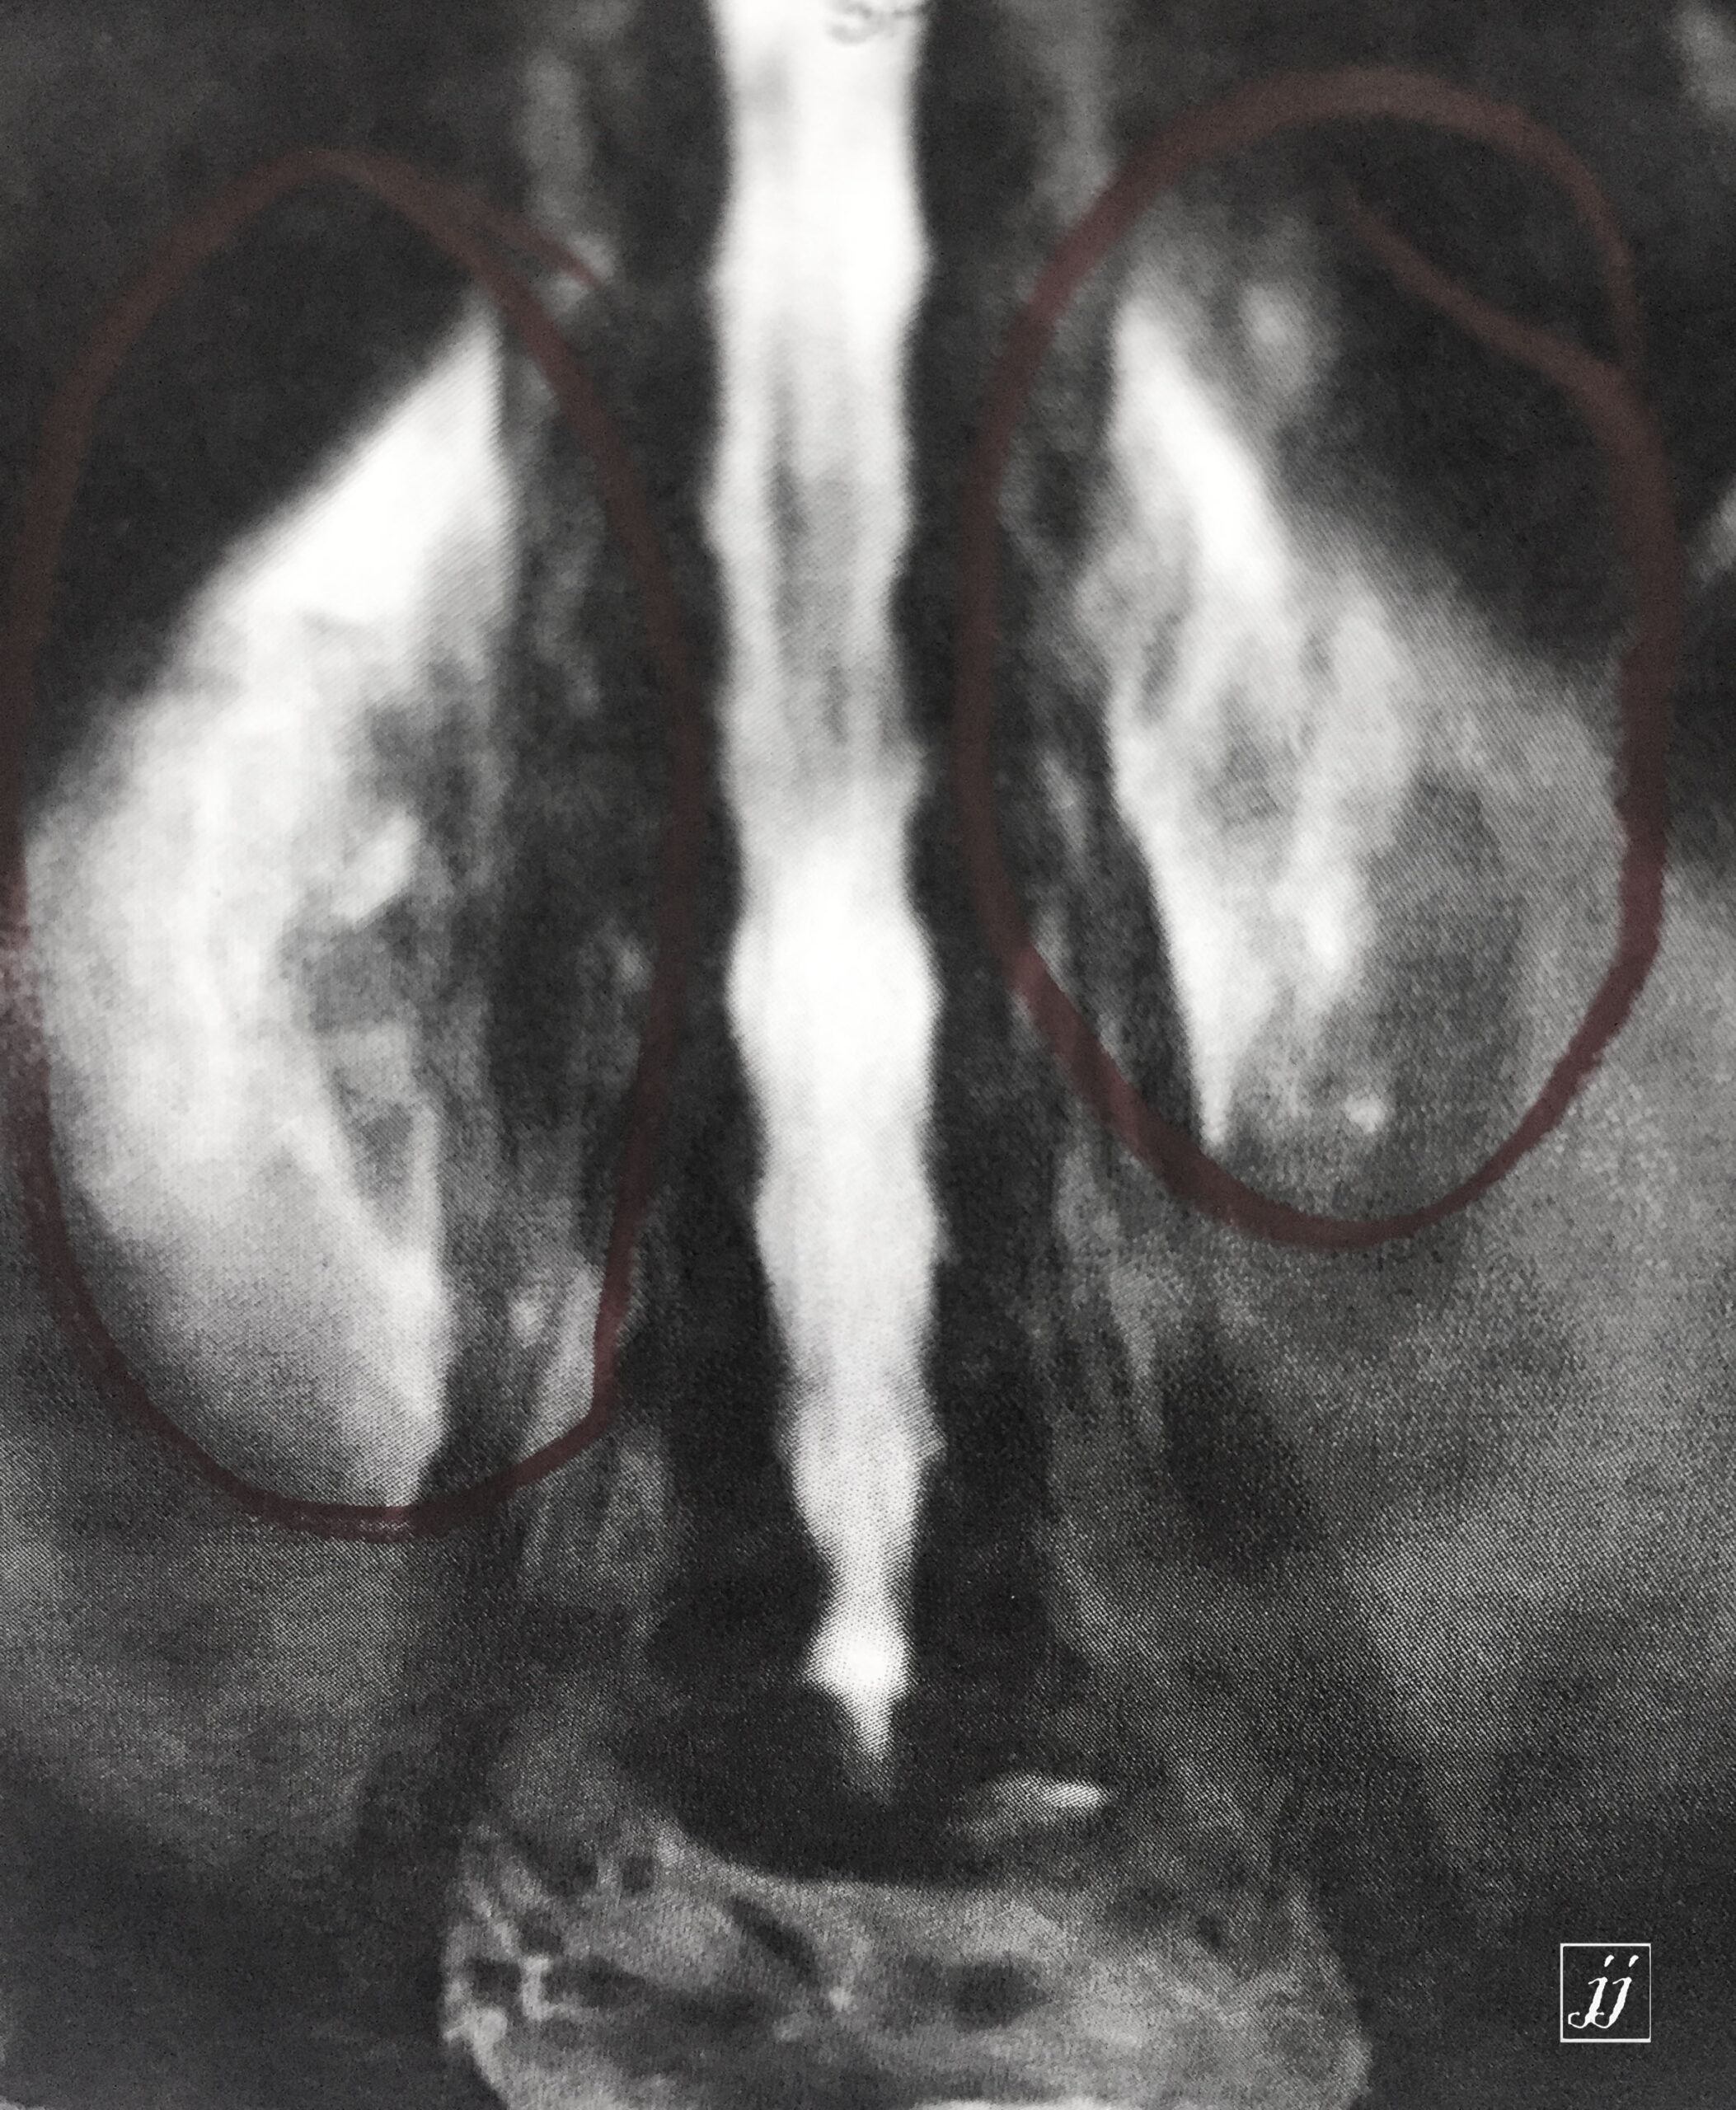

Spine- multiple vertebral body fracture and bi lateral pre renal edema (9)